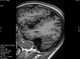

Perisylvian syndrome is a rare neurological disease characterized by damage to the sylvian fissure (lateral sulcus), an area in the brain involved in language and speech. The main symptoms are difficulty chewing and swallowing, low muscle tone in the face and tongue, speech and language development disorders, and epilepsy. [Source: Wikipedia ]